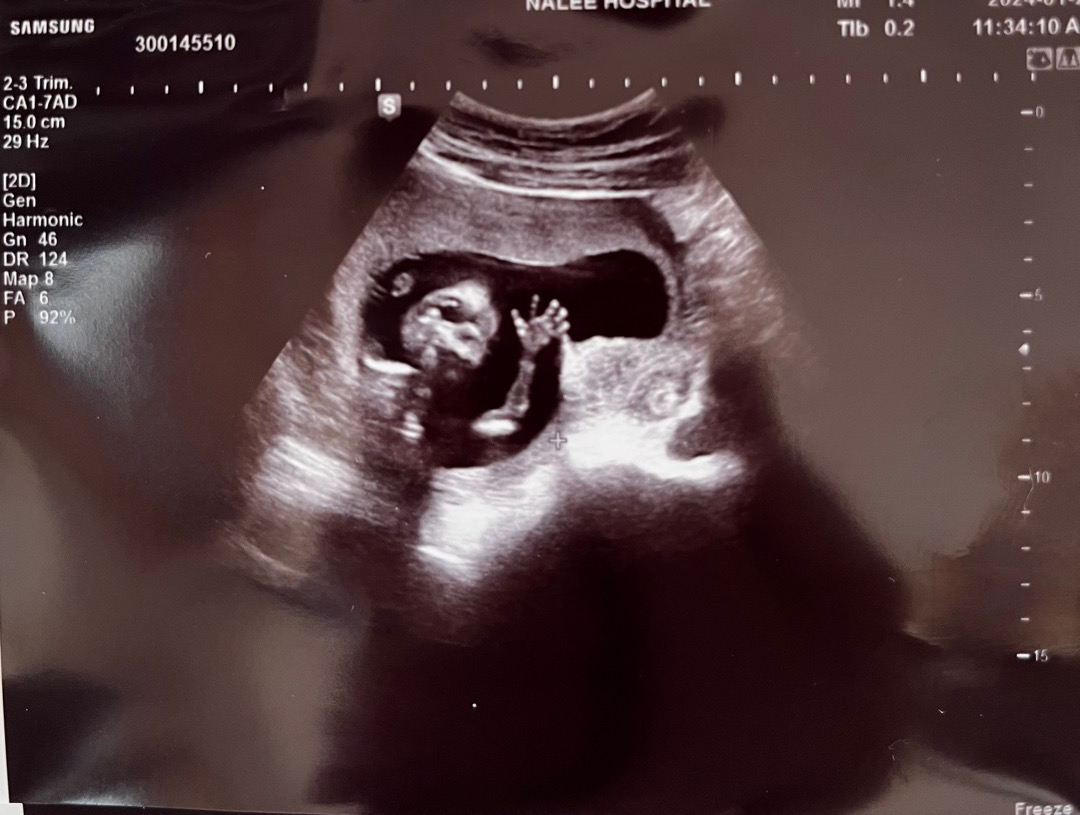

ㅋㅋㅋ촘파사진 너무 귀여워요!!!

어제 임신 16주 1일이라 원랴 다음주 병원진료인데 직장인이라 스케쥴 안맞아서 ㅠ 겨우 토요일에 대기 두시간 해서 성별 알게됐어요!! 저는 느낌이 아들같아서 약간? 확신아닌 확신?? 하고 있었는데 딸이라고 하더라규요 !!! 딸이길 바랬는데!! 건강하게만 태어났으면 좋겠어요!성별을 떠나서 건강하기만 하면 뭐든 좋을것 같아요!!! 저희또치가 정면으로 손흔들고 인사해서 너무 기분이 좋았어요^^

초음파사진 넘 특이한(?) 포즈네요!!! ㅋㅋㅋㅋㅋㅋㅋㅋ 첨보는 자센데 너무 귀여워요👶🏻ㅋㅋㅋㅋ엄마 안녕! 하는느낌 ㅋㅋ